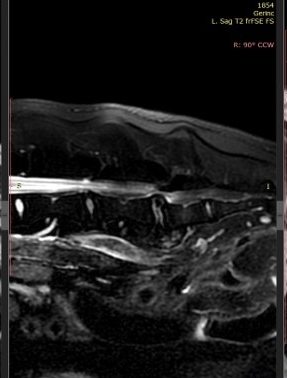

- Amennyiben rendelkezésre áll, MRI-vizsgálat is benyújtható, különösen lágyrészeket, daganatokat vagy neurológiai képleteket érintő esetekben.